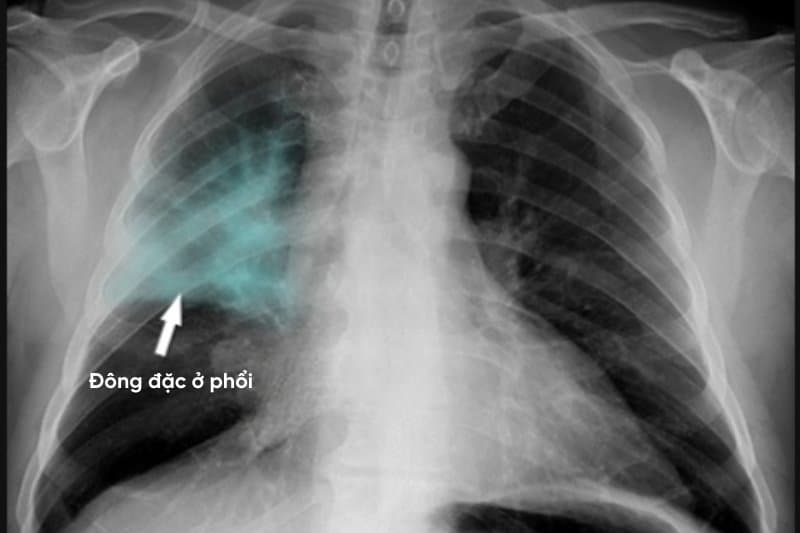

Vậy ung thư phổi chụp X quang có thấy không? Câu trả lời là có thấy những bất thường, nhưng không thể khẳng định chắc chắn đó là ác tính hay lành tính. Theo National MRI Scan, trên phim X-quang, ung thư phổi có thể xuất hiện dưới dạng một vùng mờ hoặc đậm màu hơn so với mô phổi xung quanh. Những bất thường này thường là các đốm trắng, vùng che mờ hoặc hình khối có ranh giới không đồng đều.

Ngược lại, ở giai đoạn tiến triển, hình ảnh X-quang thường rõ ràng với các khối trắng lớn, rất khó bỏ sót. Phim chụp lúc này có thể dễ dàng trả lời chụp X quang phổi có phát hiện khối u không và cho thấy các biến chứng kèm theo như tràn dịch màng phổi hoặc các vùng viêm phổi nặng. Nhiều bệnh nhân chỉ đi khám khi các triệu chứng như ho ra máu, đau ngực đã trở nên nghiêm trọng.

Sự chậm trễ trong chẩn đoán thường do các dấu hiệu ung thư dễ bị nhầm lẫn với viêm phế quản hoặc hậu quả của hút thuốc. Khi có những nghi ngờ ở giai đoạn muộn, X-quang có thể cho thấy tình trạng đông đặc phổi. Trong thực hành lâm sàng, việc chẩn đoán thường dựa vào kết hợp triệu chứng, tiền sử, kết quả chẩn đoán hình ảnh chuyên sâu và sinh thiết mô bệnh học. Vì vậy, thông tin lâm sàng và các phương pháp như CT scan sẽ mang tính quyết định hơn trong giai đoạn này.